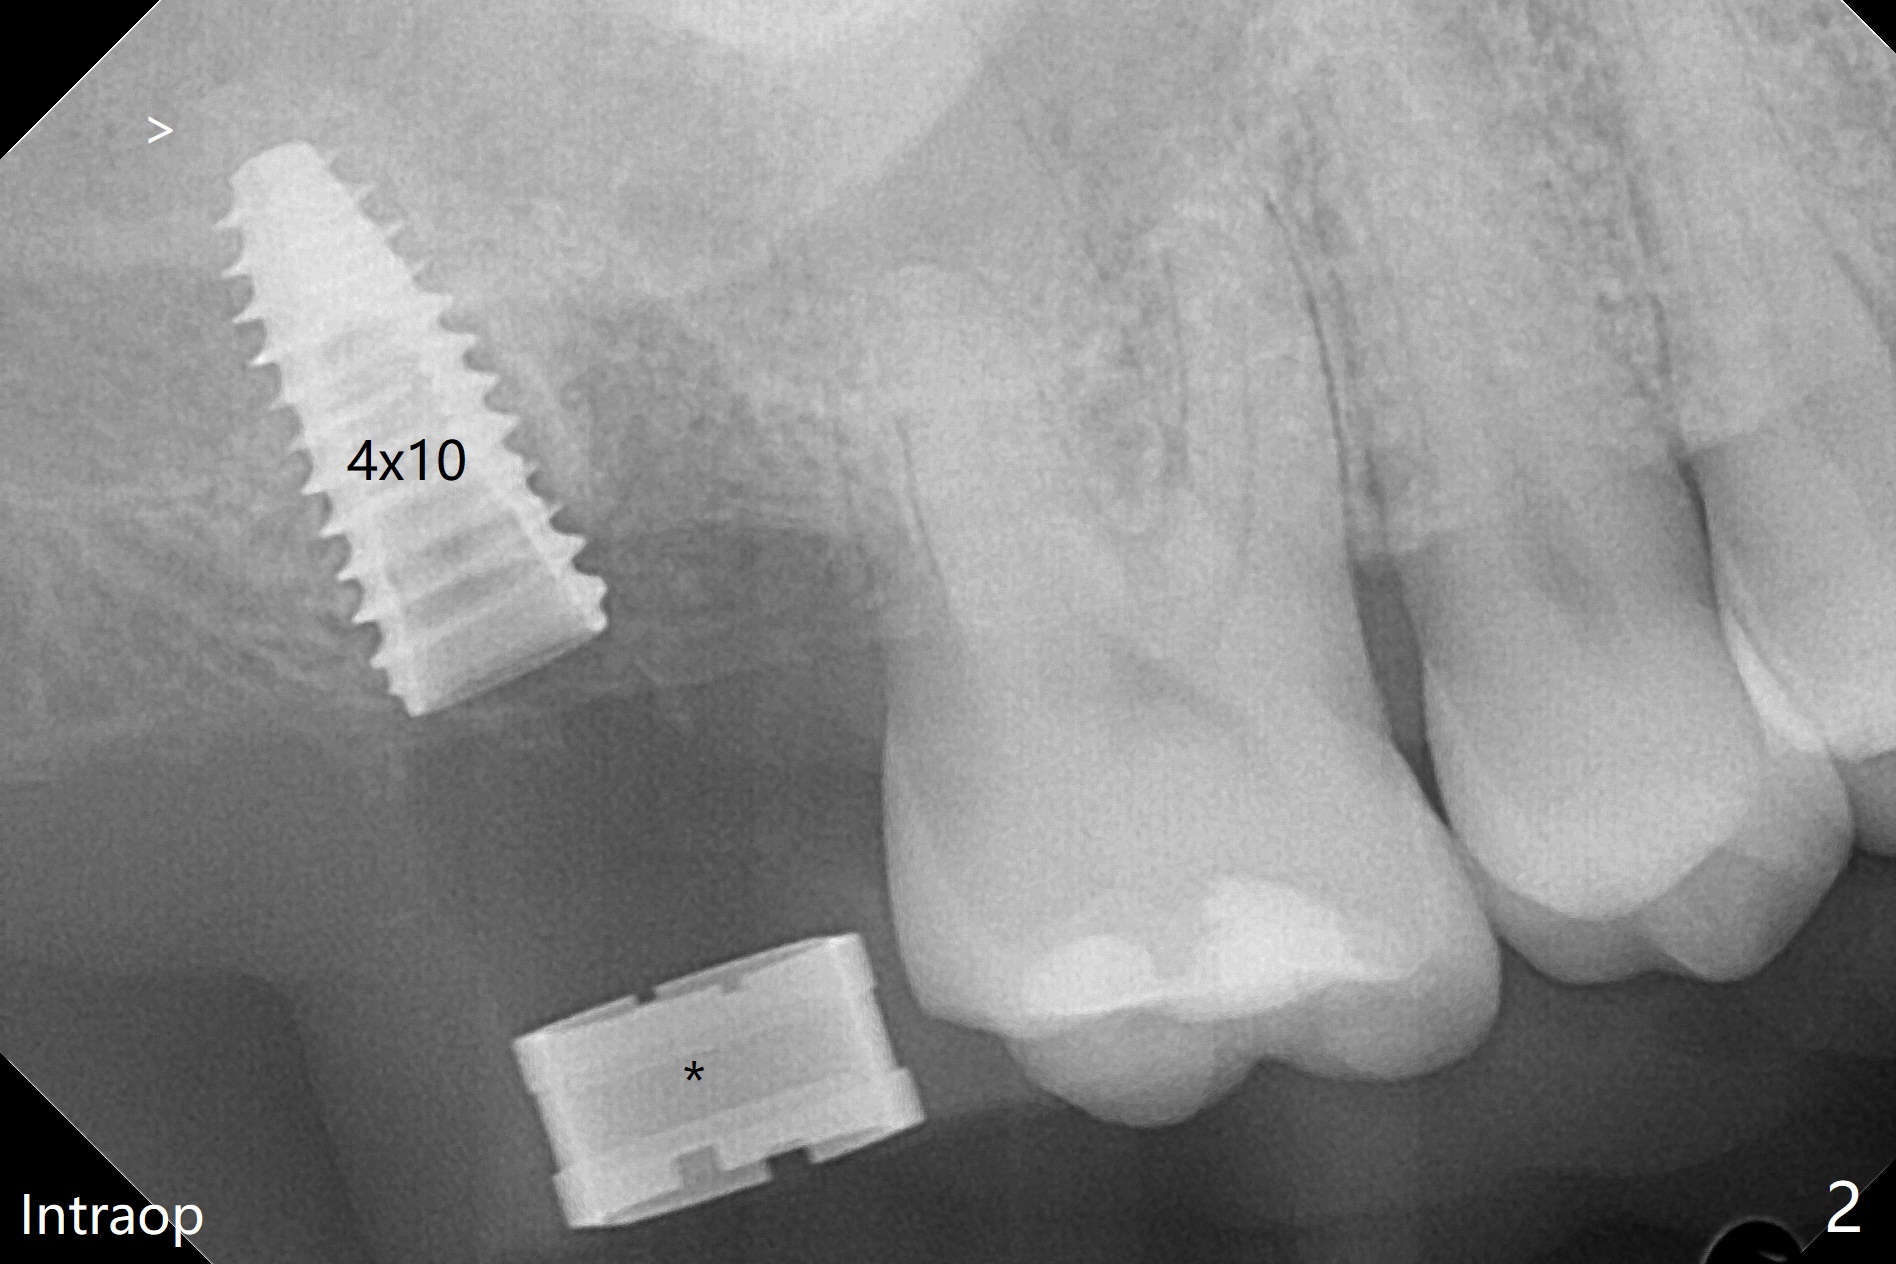

在导航协助下,我们可以一期准确进行上颌窦提升,即刻种植,即刻修复。56岁男(吸烟)右侧上颌窦有粘液囊肿,右上七牙齿折裂(图一(术前):^),CT检查表明植体植入腭侧牙槽窝比较合适(图一:>)。为了减少对囊肿损伤,我们使用导板(图二 *)完成初步钻洞,接近上颌窦底板,然后放置粘性骨(>),用4x10毫米dummy(报废)植体慢速(15 RPM)旋入进行内提升,同时准确控制深度。再次放置骨粉,使用4.5x10毫米报废植体上推;最后放置骨粉后(图三 >),植入正式植体(5x9毫米,扭力大于35Ncm)和修复基台(6.5x4(4)),怀疑后者没有完全就位,后来使用小的基台(图四,并且调整高度),植体和基台周围放置骨粉(*),然后安置临时牙冠。咬颌面没有接触,临时牙冠主要目的是防止骨粉丢失。反复告诉病人不能咬东西。术后两周病人主诉临时牙冠太大,试图减少颊舌侧向,不幸的是却减少近中远中向,造成临时牙冠不稳定。一周后牙冠和基台松动,取出,放置愈合螺帽,牙槽窝基本愈合。病人将术后近四个月复诊,拍摄根尖片和咬翼片,如果骨质愈合良好,尝试在尚未完全愈合的伤口放置小号愈合基台。术后5个月牙冠粘固后拧紧植体松动,取出(图五(*:缺损)),植骨。四个月后骨质高度近5毫米(图六)。再次植入尽量避免窦膜穿孔(粘液囊肿),塞入PRF膜。Return to Upper Molar Immediate Implant, Prevent Molar Periimplantitis (Protocols, Table) No Deviation 不理想病例 开场白Xin Wei, DDS, PhD, MS 1st edition 08/10/2020, last revision 06/12/2021